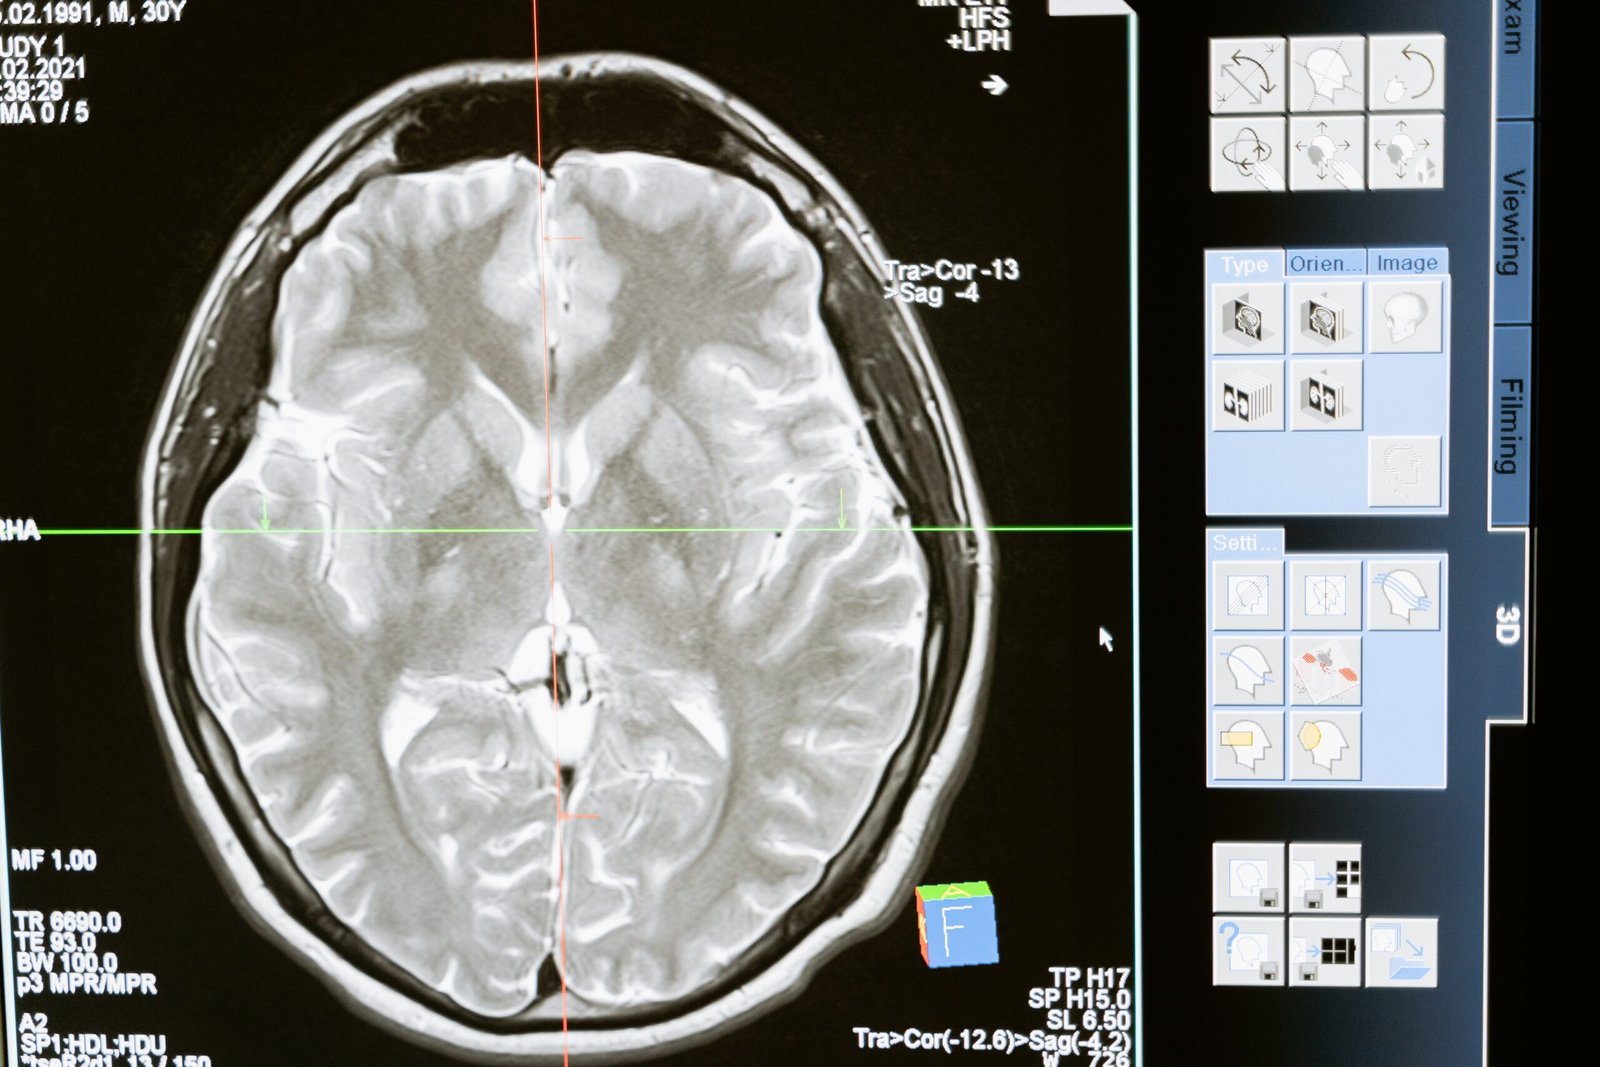

1. Magnetic Resonance Imaging (MRI):

MRI scans provide detailed images of the brain’s structure, allowing doctors to detect abnormalities such as tumors, lesions, or vascular issues. It is a non-invasive and highly versatile diagnostic tool.